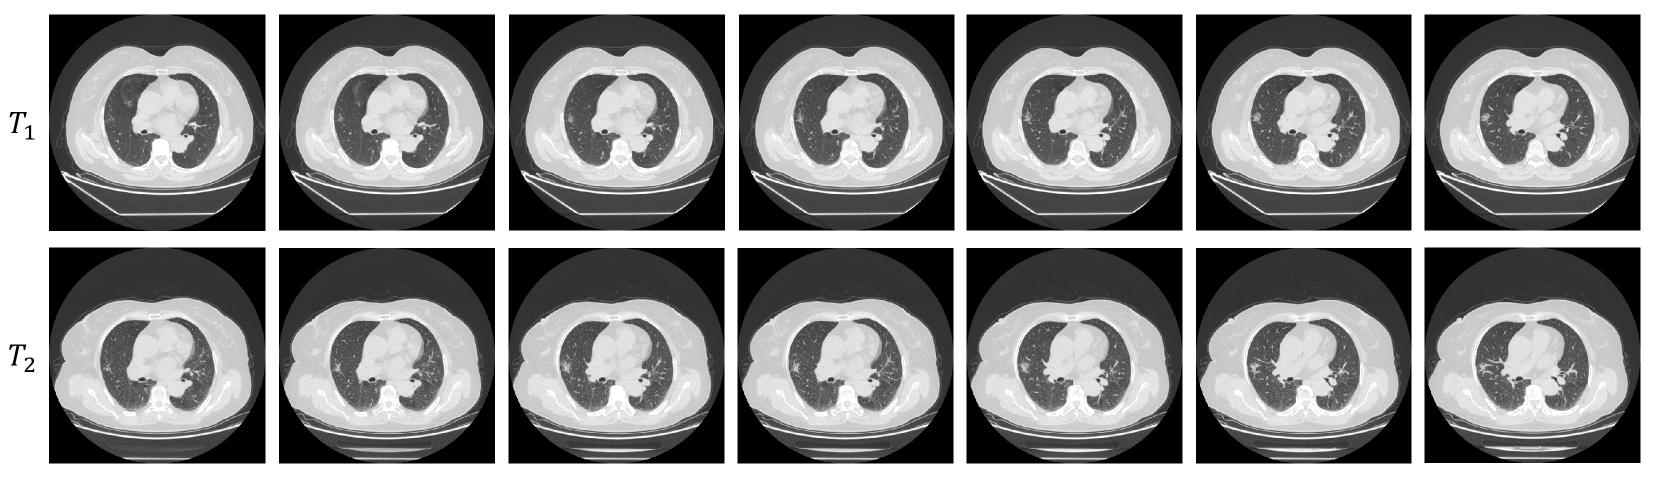

Temporal dimension CT series: We collect CT scans from patients at various time points, denoted as T1,T2,,Tmsubscript𝑇1subscript𝑇2subscript𝑇𝑚T_{1},T_{2},\cdots,T_{m}italic_T start_POSTSUBSCRIPT 1 end_POSTSUBSCRIPT , italic_T start_POSTSUBSCRIPT 2 end_POSTSUBSCRIPT , ⋯ , italic_T start_POSTSUBSCRIPT italic_m end_POSTSUBSCRIPT , where m𝑚mitalic_m represents the CT scans captured at the m𝑚mitalic_m moments for each patient. Unlike single-point-in-time slice studies, longitudinal studies yield dynamic data tend to unearth richer information about the disease variation. Fig. 2 shows an example of CT images taken at different times for an identical patient.

Figure 2: An example of the CT sequences of different temporal dimension.